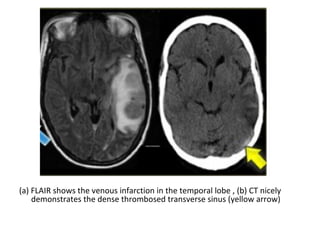

(a) FLAIR shows the venous infarction in the temporal lobe , (b) CT nicely

demonstrates the dense thrombosed transverse sinus (yellow arrow)

MRA with non-visualization of the left transverse sinus, since the venous anatomy is

variable, this can be due to absence of the transverse sinus or thrombosis, the T1

clearly demonstrates, that there is a transverse sinus on the left, so the MRA

findings are due to thrombosis

The same patient , CT shows the dense thrombosed transverse

sinus (yellow arrow) , the FLAIR shows the venous infarction

in the temporal lobe